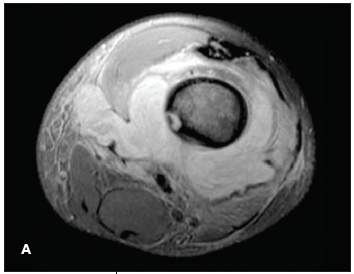

Severino R. Bautista, MD; Purushottam Gholve, MD; John P. Dormans, MD

Musculoskeletal infections in children include osteomyelitis, septic arthritis, and pyomyositis. Most of these infections are bacterial.

Musculoskeletal infections in children include osteomyelitis, septic arthritis, and pyomyositis.